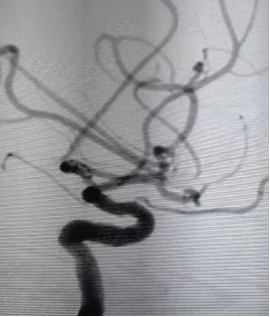

头颅CT检查结果显示,王大妈存在蛛网膜下腔出血的情况。面对这一紧急情况,德安县总医院人民医院立即启动了神经外科会诊程序,组织专家团队对王大妈的病情进行了全面评估。经过专家们的会诊,王大妈被确诊为左侧大脑中动脉瘤,并需要尽快进行手术治疗。

为确保手术的顺利进行,神经外科团队对王大妈的病情进行了进一步的详细检查,并完善了头颅CT动脉血管成像。在排除了手术禁忌后,医院决定为王大妈实施急诊脑血管造影+颅内动脉瘤栓塞术。

手术在全麻状态下进行,神经外科专家团队凭借精湛的技术和丰富的经验,成功为王大妈完成了动脉瘤栓塞术。术后,经过医护人员的精心治疗和护理,王大妈的病情逐渐趋于平稳,目前正逐步恢复中。